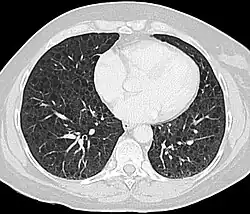

CT scan of the lungs in a patient with lymphangioleiomyomatosis showing numerous thin walled cysts within the lungs

The high-resolution computed tomography (HRCT) chest scan is better than the chest radiograph to detect cystic parenchymal disease and is almost always abnormal at the time of diagnosis, even when the chest radiograph and pulmonary function assessments are normal.[3][5][6][87] The typical CT shows diffuse round, bilateral, thin-walled cysts of varying sizes ranging from 1 to 45 mm in diameter.[5][6] The numbers of cysts varies in LAM from a few to almost complete replacement of normal lung tissue. The profusion of cysts tends to be milder in patients with TSC-LAM than S-LAM, perhaps explained in part because TSC-LAM patients typically receive earlier screening.[11] Pleural effusions are seen on CT in 12% of patients with S-LAM and 6% of patients with TSC-LAM. Other CT features include linear densities (29%), hilar or mediastinal lymphadenopathy (9%), pneumothorax, lymphangiomyoma, and thoracic duct dilation.[5][6] Ground-glass opacities (12%) suggest the presence of interstitial edema due to lymphatic congestion. In patients with TSC, nodular densities on HRCT may represent multifocal micronodular pneumocyte hyperplasia (MMPH) made up of clusters of hyperplastic type II pneumocytes.[79][88][89] MMPH may be present in males or females with TSC in the presence or absence of LAM, but not in patients with S-LAM.[90] MMPH is not typically associated with physiologic or prognostic consequences, but one case of respiratory failure due to MMPH has been reported.[91][92][93]